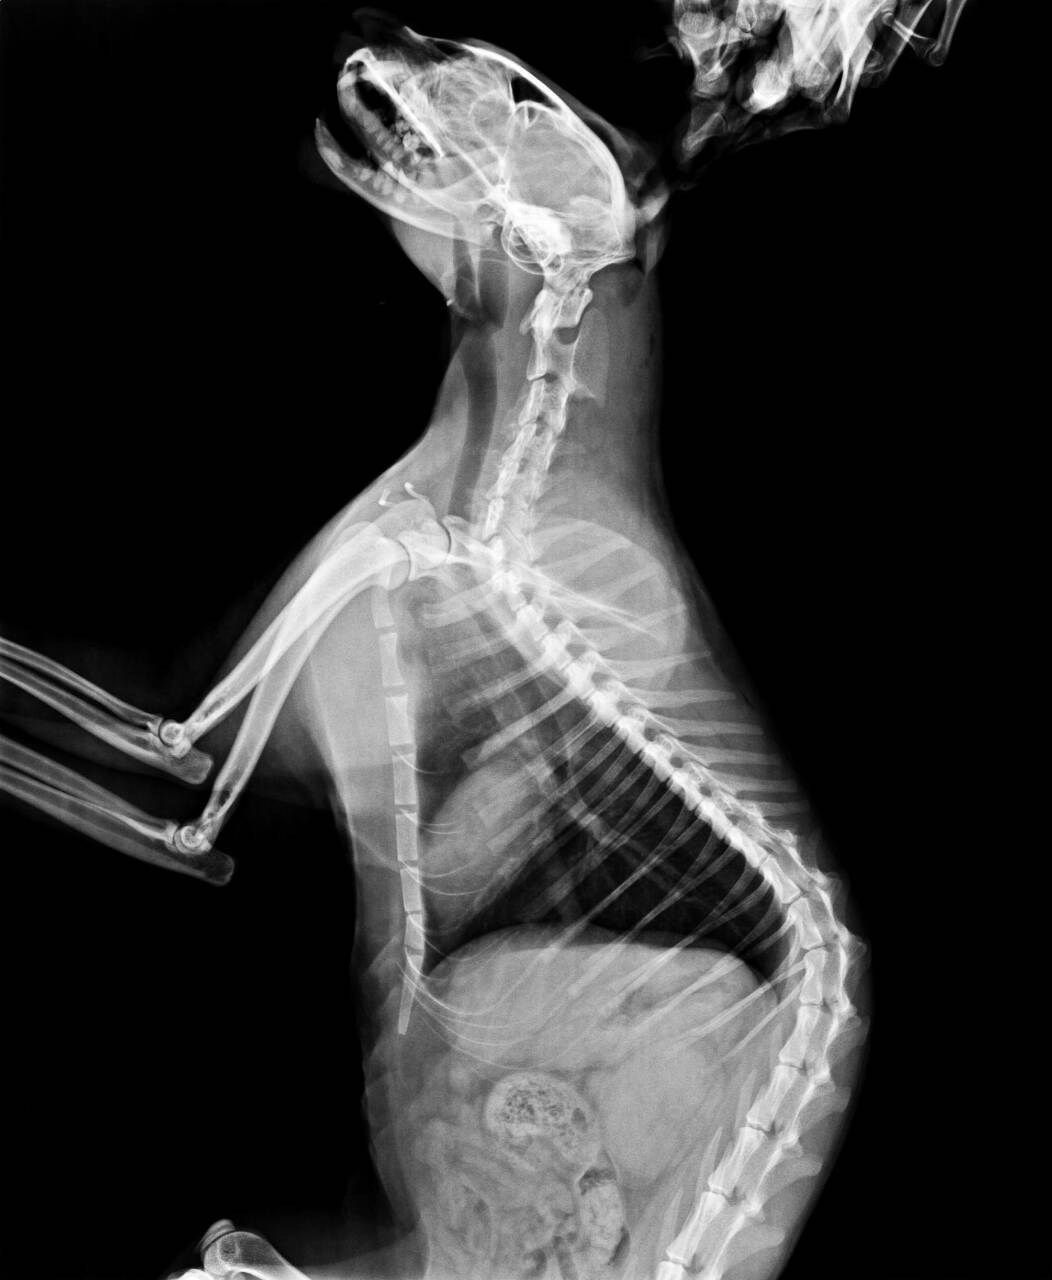

由同事幫忙送醫後,醫生表示外傷主要為下顎斷裂無法進食,無骨折,頭部進入空氣,有吐血,身體激素因求生反應,部分指數標高或偏低,疑似為車禍所致。

血檢及X光之後會再補上。動物近況說明: 12/3(四)

女護士去摸摸他發現都趴著沒有站起來,所以重新照X光檢查下半身,

發現骨盆也有受傷,在支撐點破裂(脫臼)了,整個上移了一個脊髓,所以雙腳雖然有反應但是無法撐起整個身體,這部份也需要手術治療。